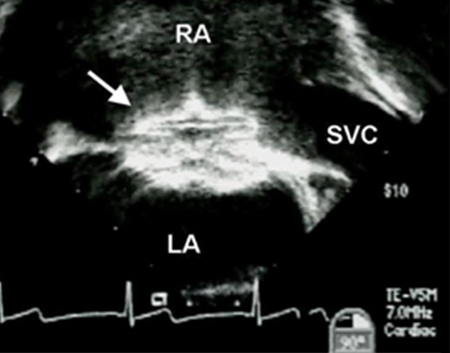

O tratamento envolve cirurgia ou fechamento por meio de um dispositivo percutâneo.[29][Figure caption and citation for the preceding image starts]: Imagem de ecocardiografia transesofágica de um dispositivo de oclusão de defeito do septo atrial (DSA) (seta). (AD) átrio direito; (AE) átrio esquerdo; (VCS) veia cava superiorImagem cedida por Patrick W. O'Leary, MD [Citation ends].